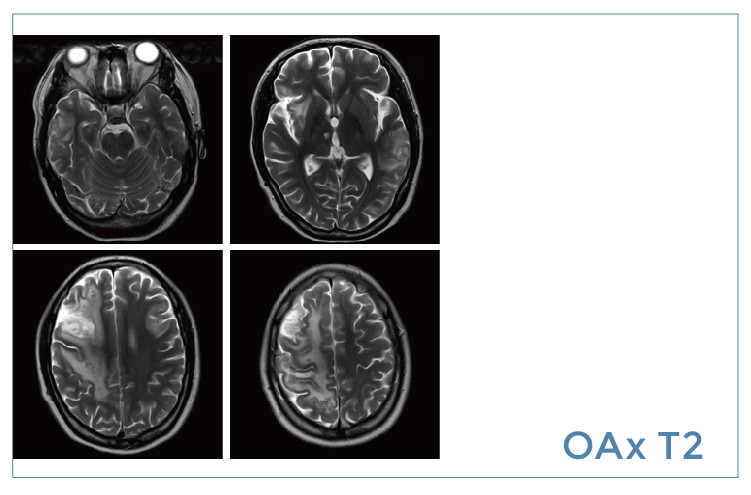

【朗润影像档案】磁共振影像病例分享(编号20191122)